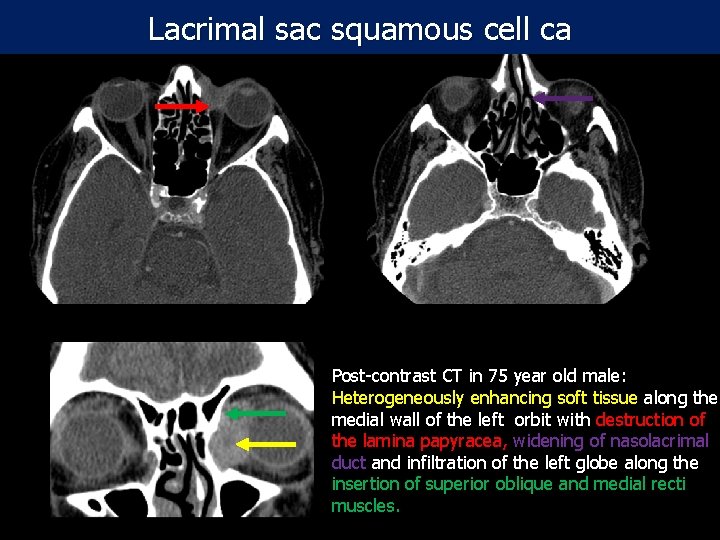

Lacrimal sac squamous cell ca Post-contrast CT in 75 year old male: Heterogeneously enhancing soft tissue along the medial wall of the left orbit with destruction of the lamina papyracea, widening of nasolacrimal duct and infiltration of the left globe along the insertion of superior oblique and medial recti muscles.